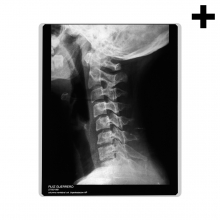

Huesos

Definición:

m. Cada una de las piezas duras que forman el neuroesqueleto de los vertebrados.